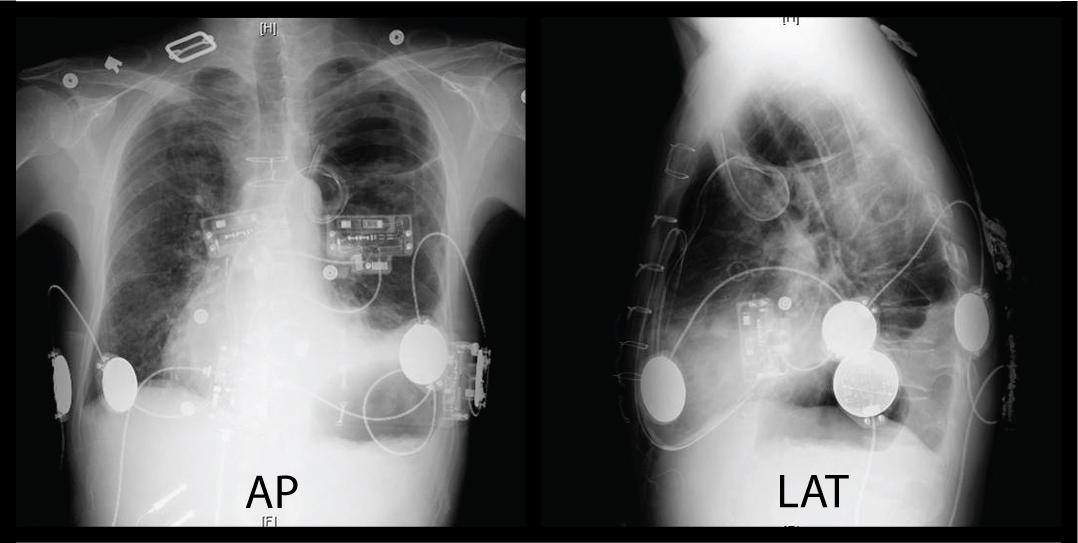

Normal CXR AP and Lateral JETem Chest X Ray Ap And Lateral Cpt  This section lists what the radiologist saw in each area of the.  ap portable view of the chest;  the current procedural terminology (cpt ®) code 71046 as maintained by american medical association, is a medical procedural.   the lateral chest view examines the lungs, bony thoracic cavity, mediastinum, and great vessels.  in this diagnostic procedure, the provider. Chest X Ray Ap And Lateral Cpt.